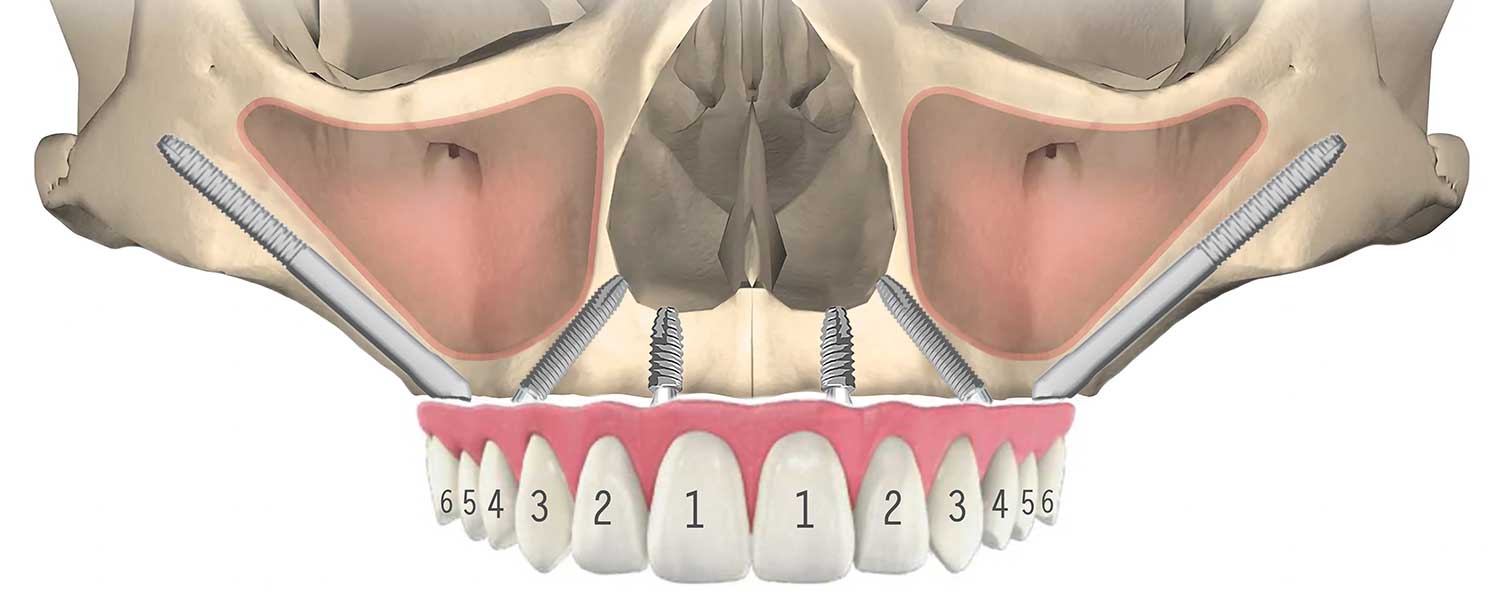

ザイゴマインプラントとは、上顎の骨が著しく吸収して通常のインプラントができない場合や、上顎洞が大きく張り出している場合に、頬骨(Zygomatic bone)を支えとして埋入する長さのある特殊なインプラントです。

通常のインプラントは一般的に6mmから18mm位ですが、ザイゴマインプラントは30mmから52.5mm(NobelBiocare)の長さがあります。

骨が無い為に、点線(⋯⋯⋯)の位置にインプラントを入れる事が出来ない(オールオン4が出来ない)場合(右側)、ザイゴマインプラントを頬骨に入れる事で、問題を解決する事が出来ます。それにより、手術と同時に仮歯を入れる事が可能となります。

前方は通常のインプラント、後方にザイゴマインプラントを用い上部構造を支える方法を、一般的にオールオンフォーハイブリッドと呼びます。

03All-on-4 Double Zygoma

前方、後方にザイゴマインプラントを用い上部構造を支える方法を、一般的にオールオンフォーダブルザイゴマやクアッドザイゴマと呼びます。上顎骨が大きく萎縮してしまったケースに対し、ザイゴマインプラントのみを用いる非常に難易度が高い治療法です。